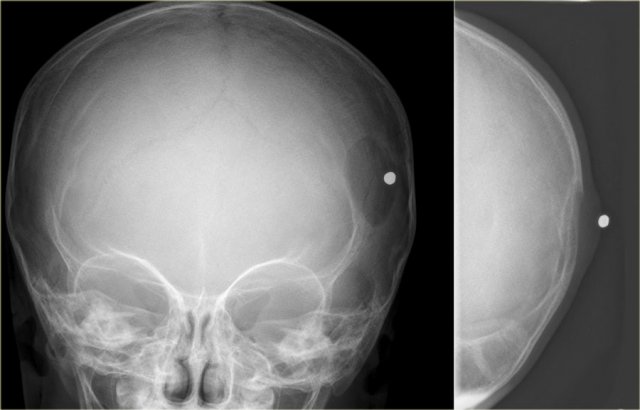

Monostotic and polyostotic eosinophilic granuloma in the skull Monostotic and polyostotic eosinophilic granuloma in the skull

Eosinophilic granuloma (3)

On the left a well-defined osteolytic lesion.

A zone of sclerosis can be seen surrounding the lytic lesion.

Sometimes a so called button-sequestrum is found in the central part.

The case on the right shows multiple ill-defined lesions in the parietal and frontal bone.

Histology revealed eosiniphilic granuloma.

In a young child with multiple lytic lesions of the neurocranium EG is the most likely diagnosis.